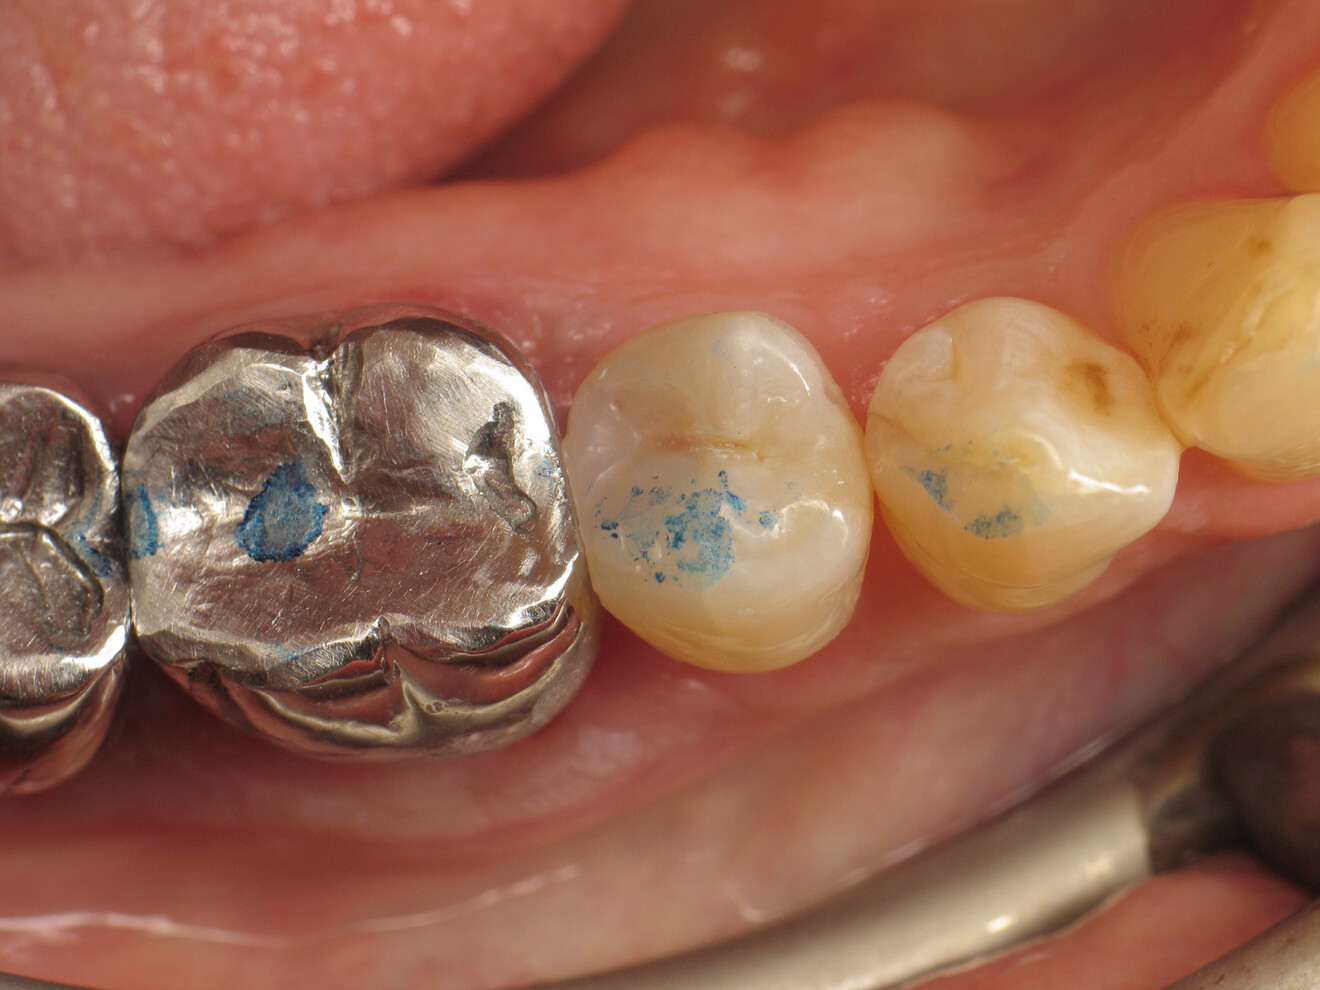

Fig. 1: Premolar with a Class II cavity. (Al images: Dr Yassine Harichane)

The clinical case described in this article concerns a Class II cavity in a premolar (tooth #45) restored using a thermo-viscous composite (Fig. 1). The tooth was isolated with a dental dam (Fig. 2). The cavity was then cleaned (Fig. 3). In order to obtain an anatomically correct distal wall, a matrix, a wedge and a ring were placed (Fig. 4). The tooth enamel was then etched for 30 seconds and the dentine for 15 seconds (DeTrey Conditioner 36, Dentsply Sirona; Fig. 5) and then rinsed and dried thoroughly (Fig. 6). Owing to the thinness of the remaining dentine, pulp protection (Telio Desensitizer, Ivoclar) was also applied (Fig. 7).

Fig. 20: Occlusion check before adjustments.

Fig. 21: Occlusion check after adjustments.